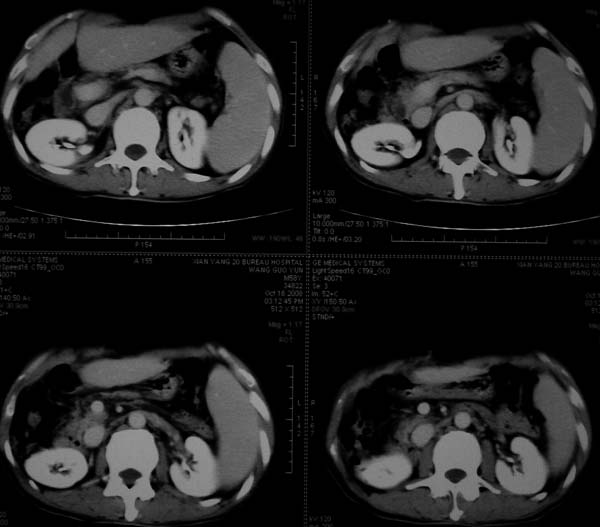

标题: CT16292:男,53岁,上腹部不适2月,B超发现肝内占位病变。 [打印本页]

标题: CT16292:男,53岁,上腹部不适2月,B超发现肝内占位病变。

符合肝ca增强,\"快进快出\";肝叶比例失常,右叶萎缩,肝裂增宽,脾大,肝硬化可能.

支持结节型肝癌。肝硬化脾大,病人是不是做过手术。

肝脏体积变小,肝裂增宽,分布异常,肝尾叶增大,脾肿大,考虑肝硬化可能性大,右肝病灶呈现早期充盈,延迟强化考虑肝内胆管细胞癌可能,不除外血管瘤

肝硬、脾大,右肾在稍息,考虑结节型肝癌可能,不排除血管瘤。

支持 结节型肝癌;肝硬化、脾大。

肝硬化,多结节肝癌。比较典型的表现了。

肝叶比例失调,左叶增大,肝裂增宽,脾脏增大,门脉增宽,肝右叶包膜下多发结节样阴影,增强虽说强化幅度不大,但还是符合快进快出特点;考虑肝硬化、脾大、结节型肝癌。胆管细胞癌多有延时强化、肝包膜凹陷征、周围胆管扩张等特点,本例明显不符;故不考虑。

支持结节型肝癌 肝硬化 脾大